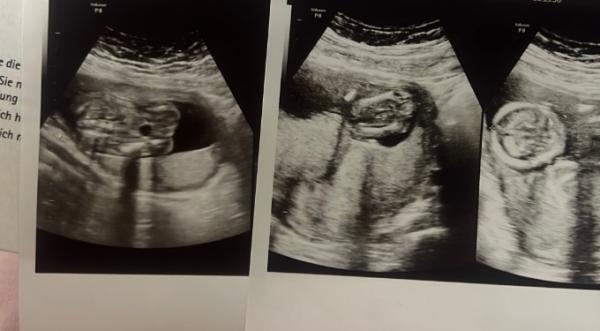

Hi, wie sieht das für euch aus :) nach Mädchen oder Junge

Also Bild 1 ist denk ich Mal der Bauchraum mit der Magenblase. Bild 3 ist der Kopf und Bild 2 Könnten zwar die Oberschenkelknochen sein aber dann komplett zusammengedruckte Beine. Keine Chance von irgendeinem Bild das Geschlecht zu erfahren.

Also bei Bild 1 hat er mir gesagt das Mädchen wird. Bei Bild 2. dachte ich die scheide zu sehen aber ja sie hat die Beine zusammen gepresst und Bild ist der Kopf